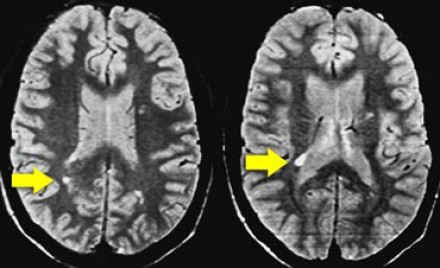

圖片三:T2加權(quán)成像和FLAIR成像

請查看上圖并描述其病變特點。我們可以看到,在T2加權(quán)成像上,在基底節(jié)上有多個高密度病灶。在FLAIR成像上,這些病灶呈黑暗模糊影,在所有序列成像上,與腦脊液的密度相近(在T1加權(quán)成像上呈低信號)。

結(jié)合信號密度和病灶部位,可以判斷是典型的血管周圍間隙。

圖片四:FLAIR成像

血管周圍間隙是穿透軟腦膜血管周圍的腦脊液間隙。通常位于基底神經(jīng)節(jié)、腦室周圍、前連合附近以及腦干中間。在MR成像圖像上,在所有序列上的密度與腦脊液的密度相近。與其他白質(zhì)損傷病灶不同,血管周圍間隙在FLAIR和PD成像上呈黑暗模糊影,通常比較小,位于前連合附近的除外,此處的血管周圍間隙比較大。

在上圖中,我們可以看到比較寬的血管周圍間隙和在白質(zhì)中有融合的高密度信號病灶。該圖像很好的顯示了血管周圍間隙和白質(zhì)損傷病灶之間的差異。

由于周圍結(jié)構(gòu)組織的萎縮,血管周圍間隙會隨著衰老和高血壓而逐漸增寬。